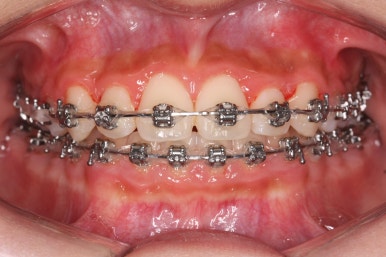

장치 부착 후에는 급속도로 치아가 가지런해지기 시작합니다.

점점 가지런해지고 있는 모습이 보이실 것입니다.

악궁 확장 이후 확보된 공간은 가지러낳게 하는데 수월함을 줍니다.

다른 앵글에서의 모습입니다.

안으로 쏙 들어가 있던 앞니가 앞으로 나오게 되면서 심미적으로 좋아지는 것을 볼 수 잇습니다.